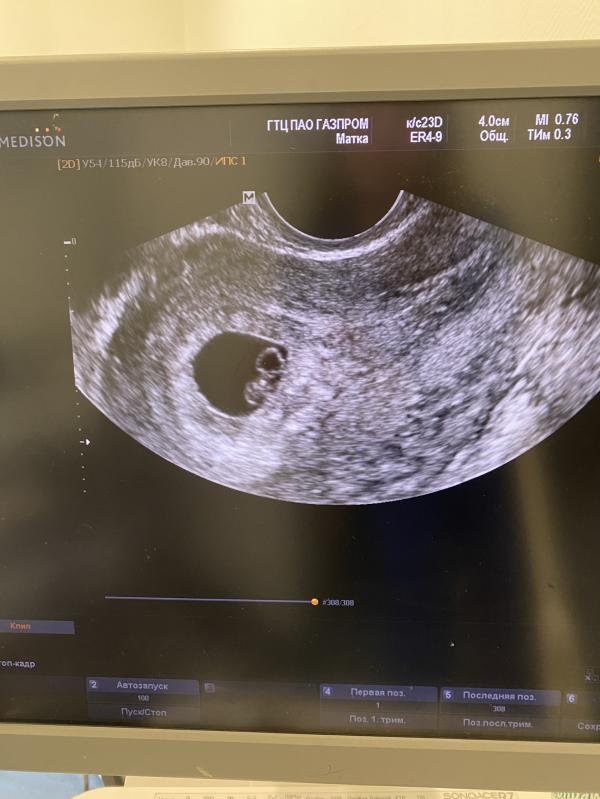

Пошли на узи 21.04. Поставили срок 8 недель по месячным (?). Поставили предположительно замершую беременность, т.к срок не соответствует размерам плода, но отправили наблюдать.

... сердцебиение 183 уд/мин, развивающаяся беременность, размер плода соответствует 6 нед и 4 дням. Включили сердце. Я порыдала, врач Панова Ольга Юрьевна клиники альпики-мед, города Сочи , предложила мне валерьянки, носовой платок и сфотографировать живого малыша для папы и родственников.